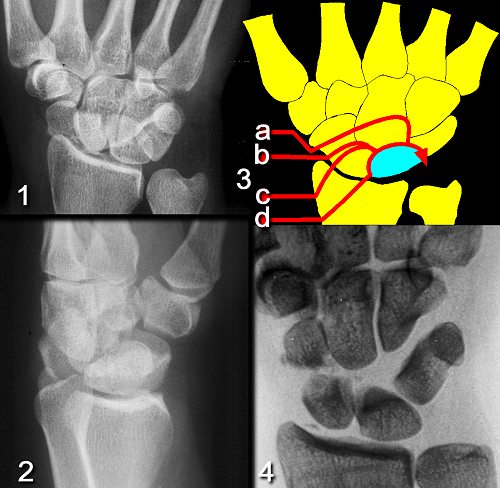

Figure Legend:

Perilunate fracture-dislocations represent high energy injuries which

are usually best treated with provisional closed reduction and then

definitive open repair. Unreduced radiographs (1,2) are usually

difficult to interpret. Many variations exist, including transscaphoid

transcapitate perilunate fracture-dislocation (3a), transscaphoid perilunate

fracture-dislocation (3b), transradial transscaphoid perilunate

fracture-dislocation (3c), and transradial

perilunate fracture-dislocation (3d). Traction films are helpful in

defining the exact pathology, as in this transscaphoid perilunate

fracture-dislocation (4).